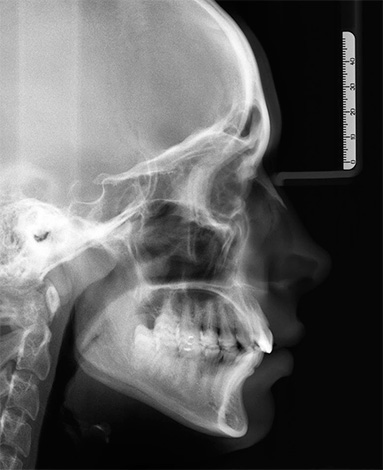

All'età di 12-14 anni e oltre, il criterio principale per fare una diagnosi corretta è lo studio di un teleradiografo della testa nella proiezione laterale. Questo tipo di studio consente al medico di farsi un'idea della natura della crescita delle ossa della mascella l'una rispetto all'altra e alla base del cranio. E anche sulla forma della patologia dell'occlusione - la malocclusione si è formata solo a causa della mancanza di spazio per i denti nell'arco dentale, oppure è dovuta al sottosviluppo e alla posizione errata delle mascelle stesse, che è correggibile, ma a volte richiede l'intervento del chirurgo maxillo-facciale.